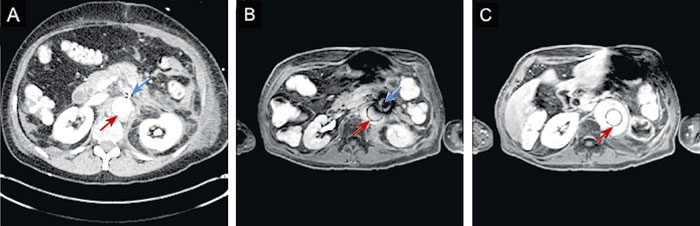

Figur 1. Patient behandlad med fenestrerad EVAR på grund av juxtarenalt aortaaneurysm, stentgraft tillverkat av rostfritt stål. DT-rekonstruktion visar stentgraftets placering (A) samt axiala MR-bilder tagna före (B) och efter (C) implantation. Snittets ungefärliga läge är markerat med streckad linje i (A). MR-bilderna togs vid 3,0 T med en T2-viktad turbospinnekosekvens.